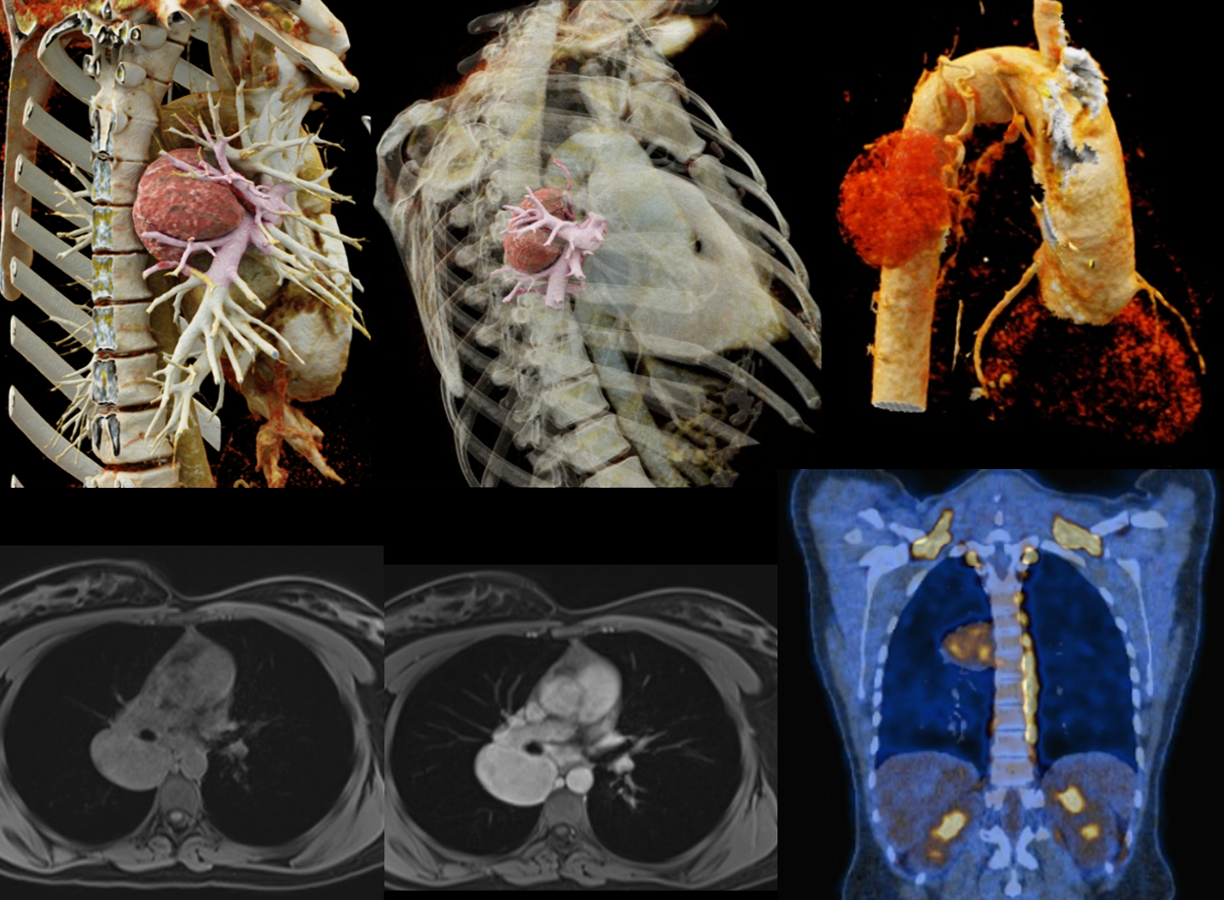

Femme de 28 ans

Douleur dorsale

Bilan réalisé:

Radiographie thoracique

Angioscanner

IRM

TEP-Scanner

QUEL EST VOTRE DIAGNOSTIC ?

A – PARAGANGLIOME

B – SCHWANNOME

C – CANCER BRONCHO-PULMONAIRE

D – MALADIE DE CASTLEMAN

E – METASTASE RÉNALE